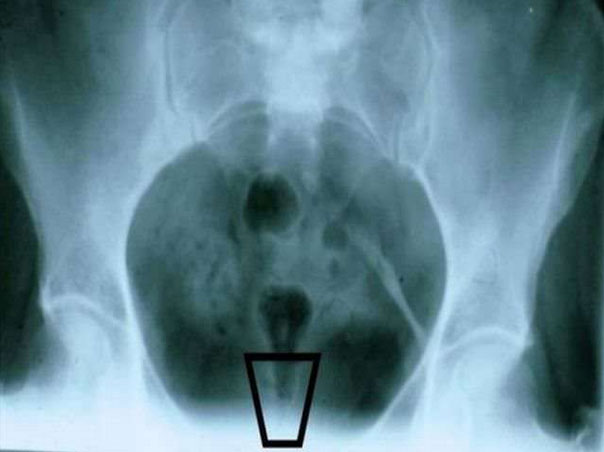

Диагностика ушиба копчика основывается на анализе анамнеза, визуальном осмотре, жалобах пациента и результатах инструментальных исследований:

- Рентгенологические исследования (рентгенография копчика в двух проекциях) проводятся после подготовки кишечника с использованием клизмы. В случаях, когда результаты остаются неясными, пациента могут направить на компьютерную томографию, предпочтительно спиральную.

- МРТ копчика назначается в основном при подозрении на ушиб, сопровождающийся образованием глубокой крупной гематомы, что позволяет детально оценить состояние окружающих мягких тканей.

Для дифференциальной диагностики ушиба и перелома копчика важным фактором является интенсивность болевых ощущений при пальпации через прямую кишку.